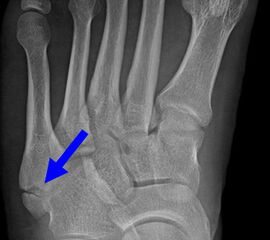

Fuß schräg ohne Belastung (45° Pronationsaufnahme)

Positionierung:

• Der Patient sitzt auf dem Untersuchungstisch.

• Der Fuß steht auf der Kassette, der laterale Fußrand wird um 45° angehoben (optional Verwendung eines Keilkissens).

• Der Zentralstrahl wird auf das Tarsometatarsalgelenk III zentriert.

• Die Röhre ist 0° vertikal ausgerichtet.

Kennzeichen des Röntgenbildes:

• Überlagerungsfreie Darstellung der Zehen und Mittelfussknochen, sowie eine gute Beurteilbarkeit der Fusswurzelknochen.

• Knochenbrücken der Fußwurzelknochen (z.B. Coalitio calcaneonaviculare) lassen sich mit dieser Aufnahme gut darstellen.

• Der Weichteilmantel ist erkennbar.

• Die 45° Pronationsaufnahme wird häufig als dritte Ebene mit belasteten Aufnahmen seitlich und dorsoplantar angefertigt.

Besondere Bemerkungen zum Beispielbild:

• Der Patient erlitt ein Mittelfußtrauma. Unter Frakturverdacht erfolgten die unbelasteten Aufnahmen.

• In der schrägen Aufnahme ist die Frakturlinie im Os cuneiforme I am besten erkennbar.

• Unauffällige Abbildung des restlichen Fußskeletts.

• Für die OP-Planung erfolgte dann noch ein Schnittbildverfahren.